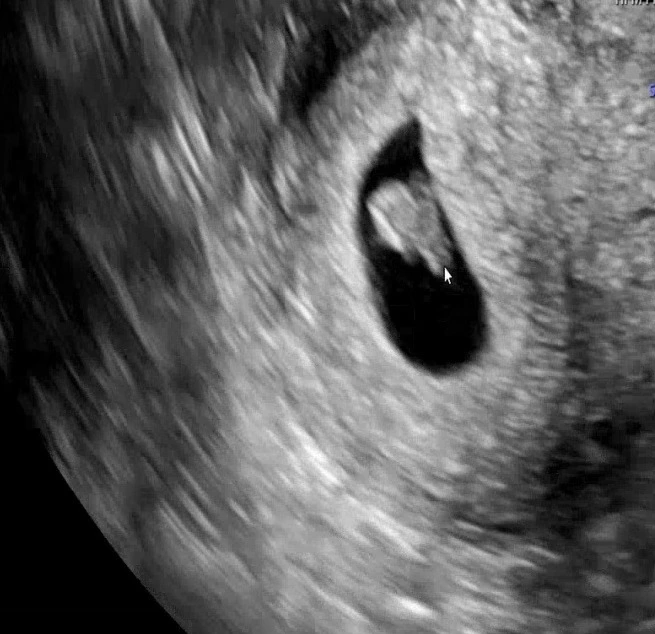

글을 쓰는 지금 36주차이니, 아기가 언제 나와도 이상하지 않을 시기다. 주위를 봐도 그렇고, 아이가 태어나면 많은 것들이 바뀔 것이다. 당연하게 여기던 조용함과 여유가 소중해질 것이라며 육아 선배님들이 겁을 주기도 하고, 그렇지만 아이가 주는 행복은 무엇과도 바꿀 수 없다는 말도 덧붙인다. 언제나 그렇듯, 이번에도 또 다시 가지 않은 길을 성큼 성큼 내닫아야만 한다.